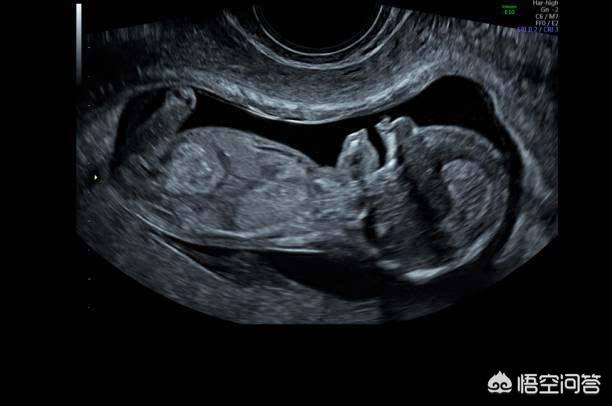

L'échographie B vérifie généralement le développement du fœtus et la position du placenta, et concerne rarement le problème des maladies fœtales. Seule l'échographie 4D permet de dépister les malformations fœtales. Votre question porte donc sur l'échographie 4D et non sur l'échographie B.

L'échographie permet de vérifier si la position du fœtus est normale, si le volume du liquide amniotique est anormal, si le cordon ombilical du fœtus est enroulé autour du cou, si le développement du fœtus est retardé et si le placenta est bas.

L'échographie pendant la grossesse permet principalement de vérifier la croissance et le développement du fœtus, son activité physiologique, la quantité de liquide amniotique et l'état du placenta.

L'échographie est utilisée pour détecter les problèmes liés au placenta, au fœtus, au liquide amniotique et au cordon ombilical. Elle constitue un élément important de l'examen de maternité qui accompagne toute la grossesse.